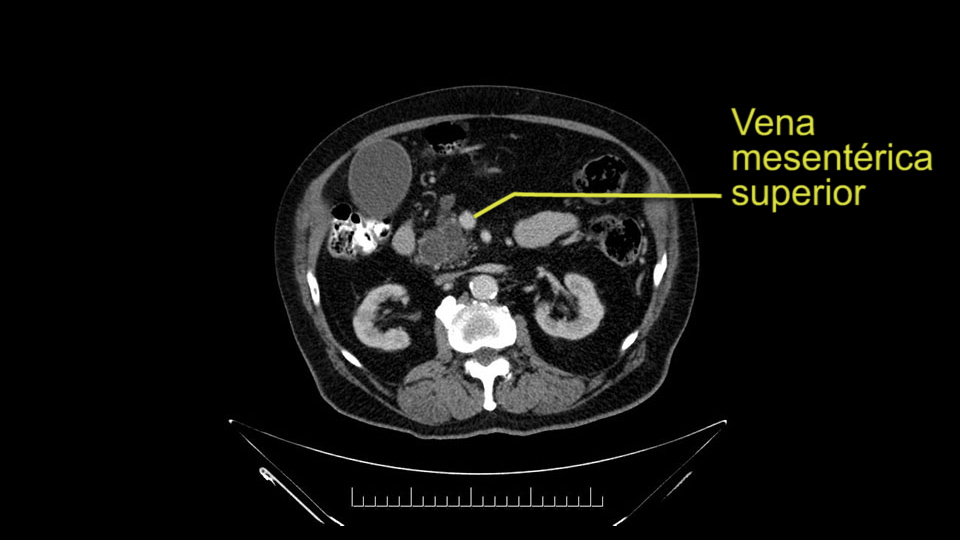

The next item that I would look at: the issue would be the vessels and usually start at the portal vein, watch the portal vein, follow it down, down-down-down to the neck of the pancreas - which is here - and there’s no impingement by tumor, which is great. The SMV and the splenic vein, which is here. The splenic vein junction is normal, which is great.

Then look at the first jejunal branch - which is this thing here - this little branch which goes under the SMA. It’s something that we’ve just started appreciating over the past few years and the reason for that is: there’s two or three small branches that come out of the uncinate into the the first jejunal and it’s a fairly inevitable part of the operation where there’s some bleeding. As long as you’re cognizant of what’s happening, it’s no reason to panic and that kind of bleeding will eventually stop or can be stopped but it’s not easy because these little vessels are fragile from the uncinate to the first jejunal. So I do focus on that and it’s pretty consistent I’d say 9 times out of 10, people have that first jejunal.

In planning for my further steps, the first key that I find, first do a gentle mobilization of the hepatic flexure of colon completely away because that’s going to help me do a good wide Kocher maneuver. Why do I slow down? Because there are small tributaries and small blood vessels which communicate between the transverse mesocolon and the head of the pancreas and you also have the loop of Henle all the blood vessels which drain into the superior mesenteric vein just as it gets underneath the neck of the pancreas.

The initial hepatic flexure mobilization and the Kocher procedure is then going to enable me to understand the uncinate process of this patient, which should not be a problem, again. But the initial pictures had shown a degree of touching. I would not even say involvement or abutment; a degree of touching with the superior mesenteric vein. So that would give me an early chance to assess how the superior mesenteric vein is in this patient. So this would be the initial slowing down moment.

The next thing we always evaluate, although we do not expect invasion to the portal veins in this case, we must always trace the path of the portal vein, in both directions, from top to bottom. The splenoportal confluence and the superior mesenteric vein, which in this case does not appear to be compromised.

Por otro lado, siempre evaluamos -aunque en este caso no esperamos que haya invasión de los vasos portales-, siempre hay que hacer el recorrido de la vena porta, en ambos sentidos, de arriba hacia abajo; el confluente esplenoportal y la vena mesentérica superior, que en este caso no aparentan estar comprometidos.

SMV dissection at pancreatic neck

The first steps of a pancreaticoduodenectomy involve ensuring the CT findings are correct: exploring for signs of metastatic disease, peritoneal implants involving the omentum or the undersurface of the diaphragm and if again this is confirmed exploration that there's no metastatic disease, I begin the mobilization and really determining the relationship of the tumor with the major visceral vessels. I start by an extended Kocher maneuver, identify the superior mesenteric vein below the neck of the pancreas. They’re very thin walled vessels and as you're dissecting you have to use the ultimate care and meticulously dissect the superior mesenteric vein, ligate the anterior branches and begin the dissection from below to under the neck of the pancreas. At this point, if there's no reason to be concerned about whether there is any vascular invasion below, I usually take the gallbladder down. I mobilize the common hepatic duct above the insertion of the gallbladder. This patients already has a stent in place. So I would divide the bile duct at this point. This facilitates the dissection of the anterior surface of the portal vein and as I would expect looking at this imaging that there is nothing to be concerned about in terms of vascular involvement.